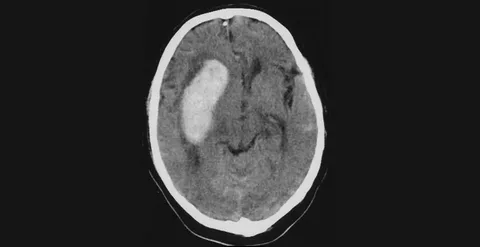

Теперь по поводу вариантов инсульта. С ростом систолического давления возрастает риск внутримозгового кровоизлияния, но в популяции преобладают ишемические инсульты. Для них уже диапазон 140–160 является значимым фактором риска, особенно при сочетании с сахарным диабетом, ожирением, курением и фибрилляцией предсердий. Распространенность этих сочетаний при умеренной гипертензии формирует основной вклад в общую заболеваемость инсультом.